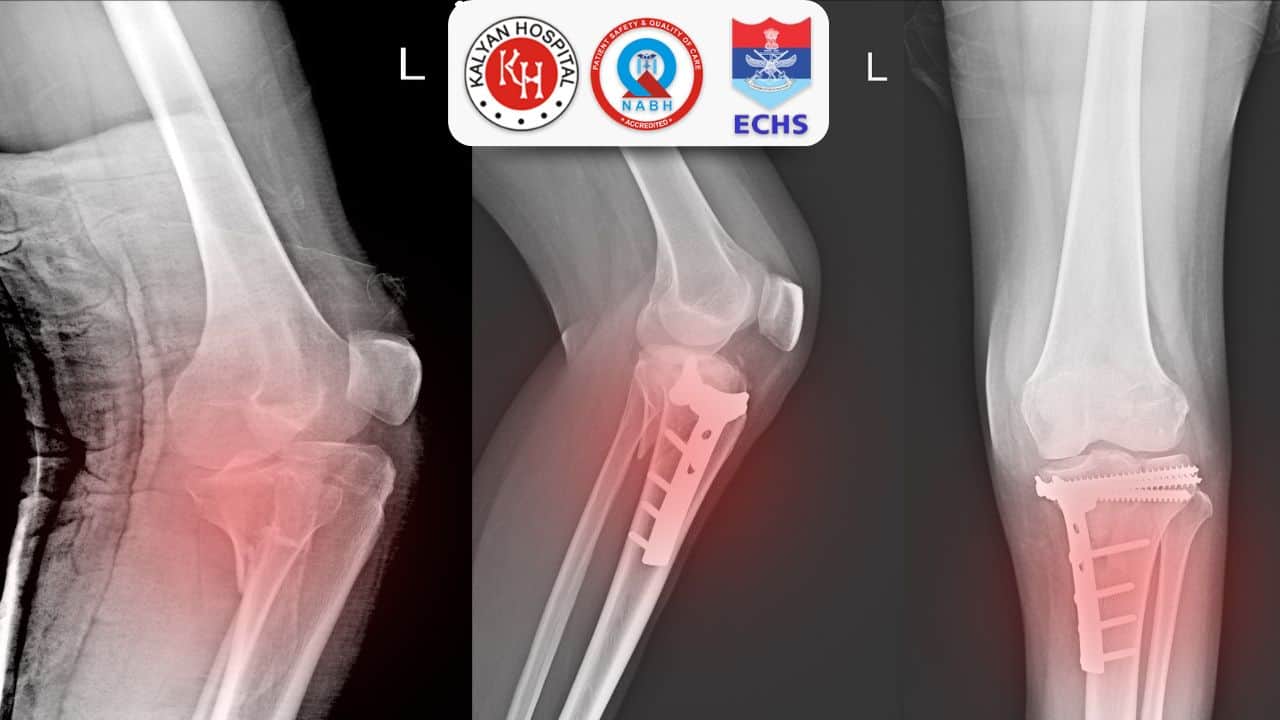

- निदान की पुष्टि करने के लिए, आपको डॉक्टर द्वारा एमआरआई, एक्स-रे या फिर न्यूक्लियर बोन स्कैन करवाने का सुझाव दिया जा सकता है |

ऐसी स्थिति में जटिलताओं को रोकने के लिए पीड़ित व्यक्ति को तुरंत चिकित्सा की आवश्यकत होती है | हेयरलाइन फ्रैक्चर के उपचार के विकल्प में आराम, कास्ट, स्पिल्ट, ब्रसेस और बैसाखी के साथ-साथ स्थितिकरण भी शामिल हो सकता है | यदि फ्रैक्चर पर्याप्त रूप से ठीक होने में असमर्थ हो जाता है, तो इसके इलाज के लिए सर्जरी को करवाने की आवश्यकता भी पड़ सकती है | लेकिन यह पूर्ण रूप से आपकी स्थिति पर निर्भर करता है |